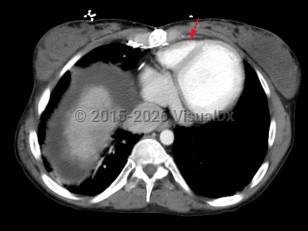

Tricuspid atresia

Congenital lack of tricuspid valve formation resulting in cyanosis and a murmur. An atrial septal defect, hypoplastic right ventricle, and ventricular septal defect are generally present. Other congenital lesions such as transposition of the great arteries may also be present. About half of cases present with cyanosis and a murmur on the day of birth. An additional 30% are diagnosed in the first month. With advances in fetal ultrasound, tricuspid atresia can be diagnosed on antenatal screening at 18-22 weeks gestation. If untreated, mortality is very high with 1-year survival estimated at 10%.

Tricuspid atresia